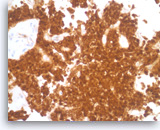

Pancreatic endocrine neoplasm #1,

Pancreas FNA, Cell Block.

The tumor cells are also positive for chromogranin, another neuroendocrine marker, with a granular cytoplasmic staining pattern.

40X

Pancreatic endocrine neoplasm #1,

Pancreas FNA, Cell Block.

The tumor cells are also positive for chromogranin, another neuroendocrine marker, with a granular cytoplasmic staining pattern.

40X